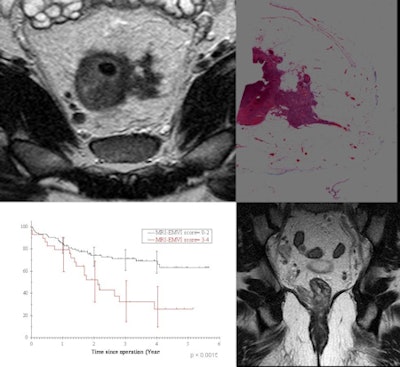

| MRI depicts the characteristic features of extramural venous invasion -- a poor prognostic factor seen in up to 30% of rectal cancer patients and associated with a 25% relapse-free survival. Detection of such high-risk patients may enable more intensive preoperative therapy and follow-up to reduce deaths related to metastatic disease. (Provided by Dr. Gina Brown) |

MRI exams have had an impact on how high-risk patients are staged by identifying features that place them at risk for metastatic disease. At the Royal Marsden, radiologists who identify biological risks shown on images that are known to cause local failure and or distant metastases to occur are part of a multidisciplinary team who evaluate if more aggressive treatment is needed.

"From our outcome data, when tumors have spread more than 5 mm beyond the muscularis, there is a massive drop in disease-free survival and overall survival. A tumor invasion in the vein that can be identified by MRI is associated with only a 25% chance of disease-free survival. In addition to the aggressive therapy we prescribe from the findings in the original MRI exam, with regularly scheduled follow-up imaging, we can monitor the post-treatment outcomes. If disease occurs, such as liver metastasis, we can identify this promptly and remove it, giving the patient a better chance of longer survival," she added.